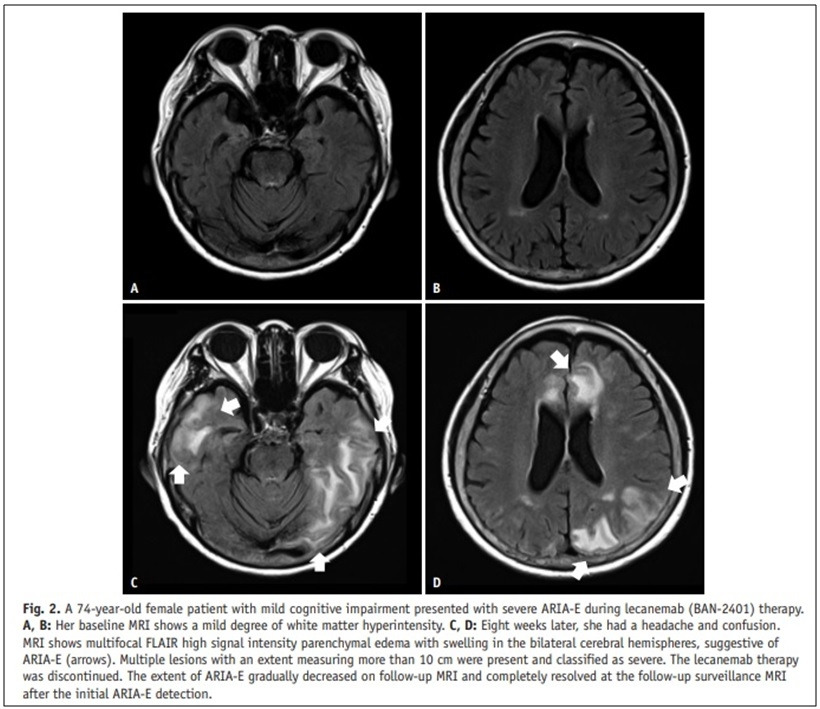

세가지 약들은 모두 뇌 속의 아밀로이드를 제거하는 작용을 하기에, 심각한 부작용인 'ARIA' 가 20-30%의 환자에서 나타난다(*아래 뇌 MRI 사진 설명 -> 74세 여성으로 레카네맙 투여 2달 후 '뇌부종'으로 인한 두통 및 정신착란 상태 발생, 투약 중단 함) [22].

SY Jeong, et al. Korean Journal of Radiology 2024

22. SY Jeong, CH Suh, SJ Kim, et al. Amyloid-related imaging abnormalities in the era of anti-amyloid beta monoclonal antibodies for Alzheimer’s disease: recent updates on clinical and imaging features and MRI monitoring. Korean Journal of Radiology 2024;25(8):726.